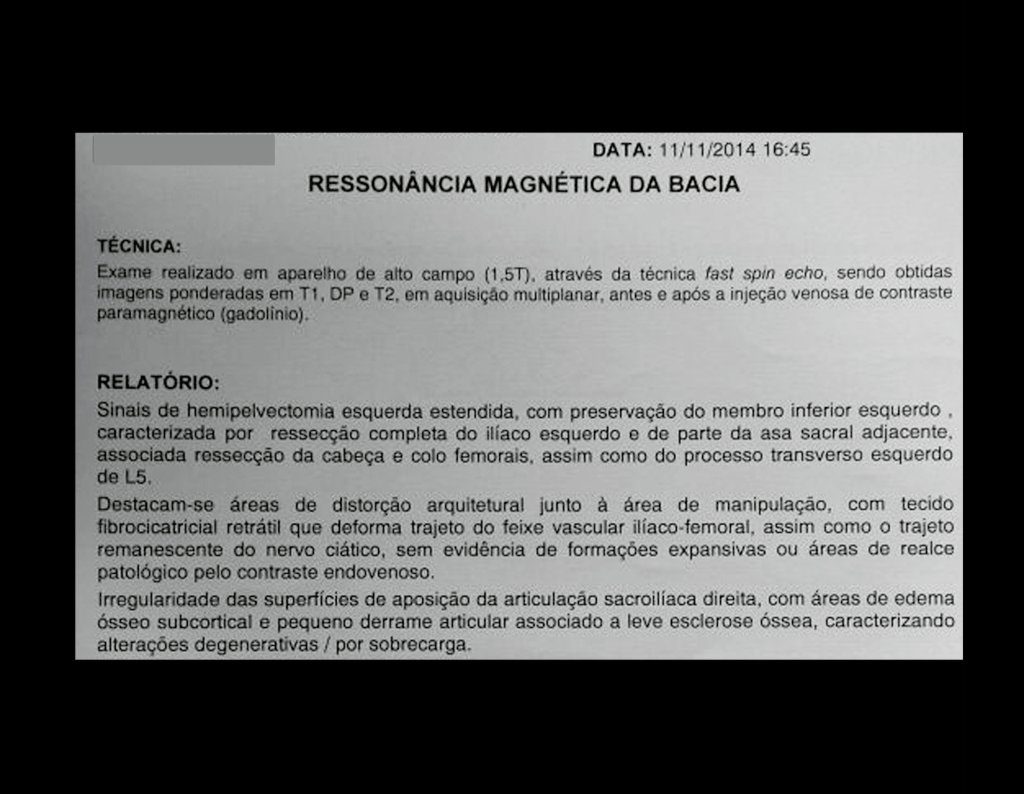

Ressonância Magnética (RM)

- RM axial e coronal em T1: Apresentou baixo sinal com grande tumor extra cortical, comprometendo a tábua interna e externa do ilíaco direito.

- RM axial e coronal em T2: Sinal alto com grande tumor extra cortical.

- RM axial T1 spir: Com supressão de gordura, evidenciou reação periosteal em espículas e focos de calcificação.

- RM axial T1 com saturação de gordura e contraste: Mostrou uma espessa área de captação devido à capa de cartilagem neoplásica maligna ao redor da lesão.

- Dois anos pós-operatório: RM sem sinais de recidiva, bom aspecto local.